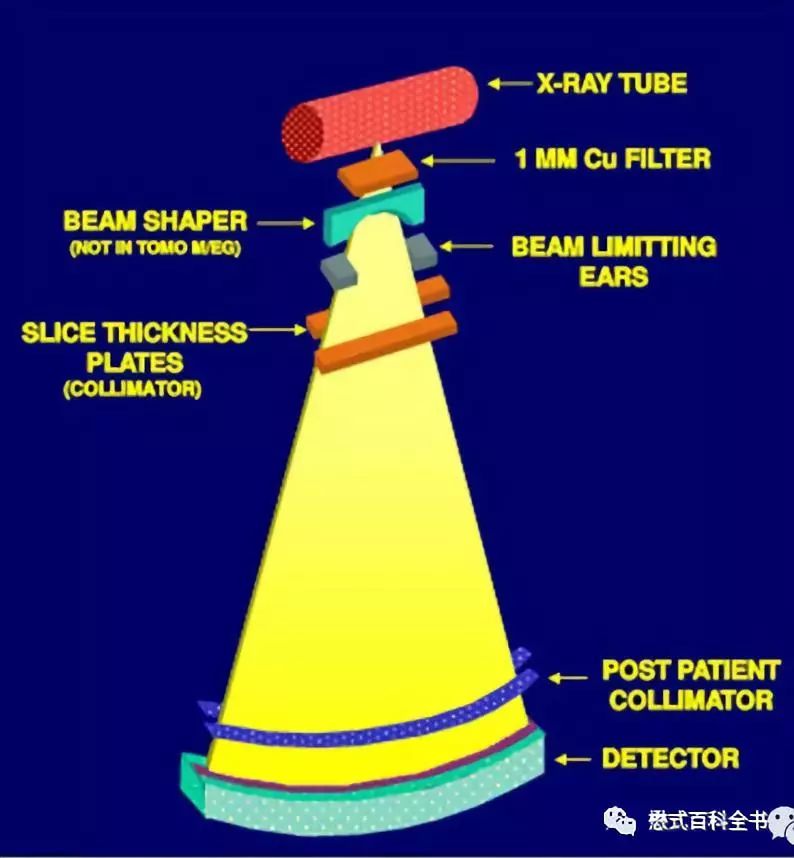

图6:传统的X线成像

第一次飞越是由非螺旋CT发展为螺旋CT,英文Spiral CT或Helical CT,主要的技术革新是利用了滑环技术,探测器可以连续旋转,这次飞越使CT摆脱了逐层扫描的模式。传统的非螺旋CT扫描模式采用的是进步-采集模式,即step-and-shot。这种采集方式包含了两个周期:数据采集周期和非数据采集周期。在数据采集周期,病人不动(扫描床位置不动),X线球管和探测器以一定速度绕病人旋转一周,采集数据;当一层数据采集完成以后,进入非数据采集周期,扫描床移动到下一个扫描位置,等待新的数据采集周期。可以发现,螺旋CT出来之前,CT扫描是采用逐层扫描进床的模式,扫描速度非常慢,而且容易产生伪影,也不方便做一些受呼吸运动影响大的部位。